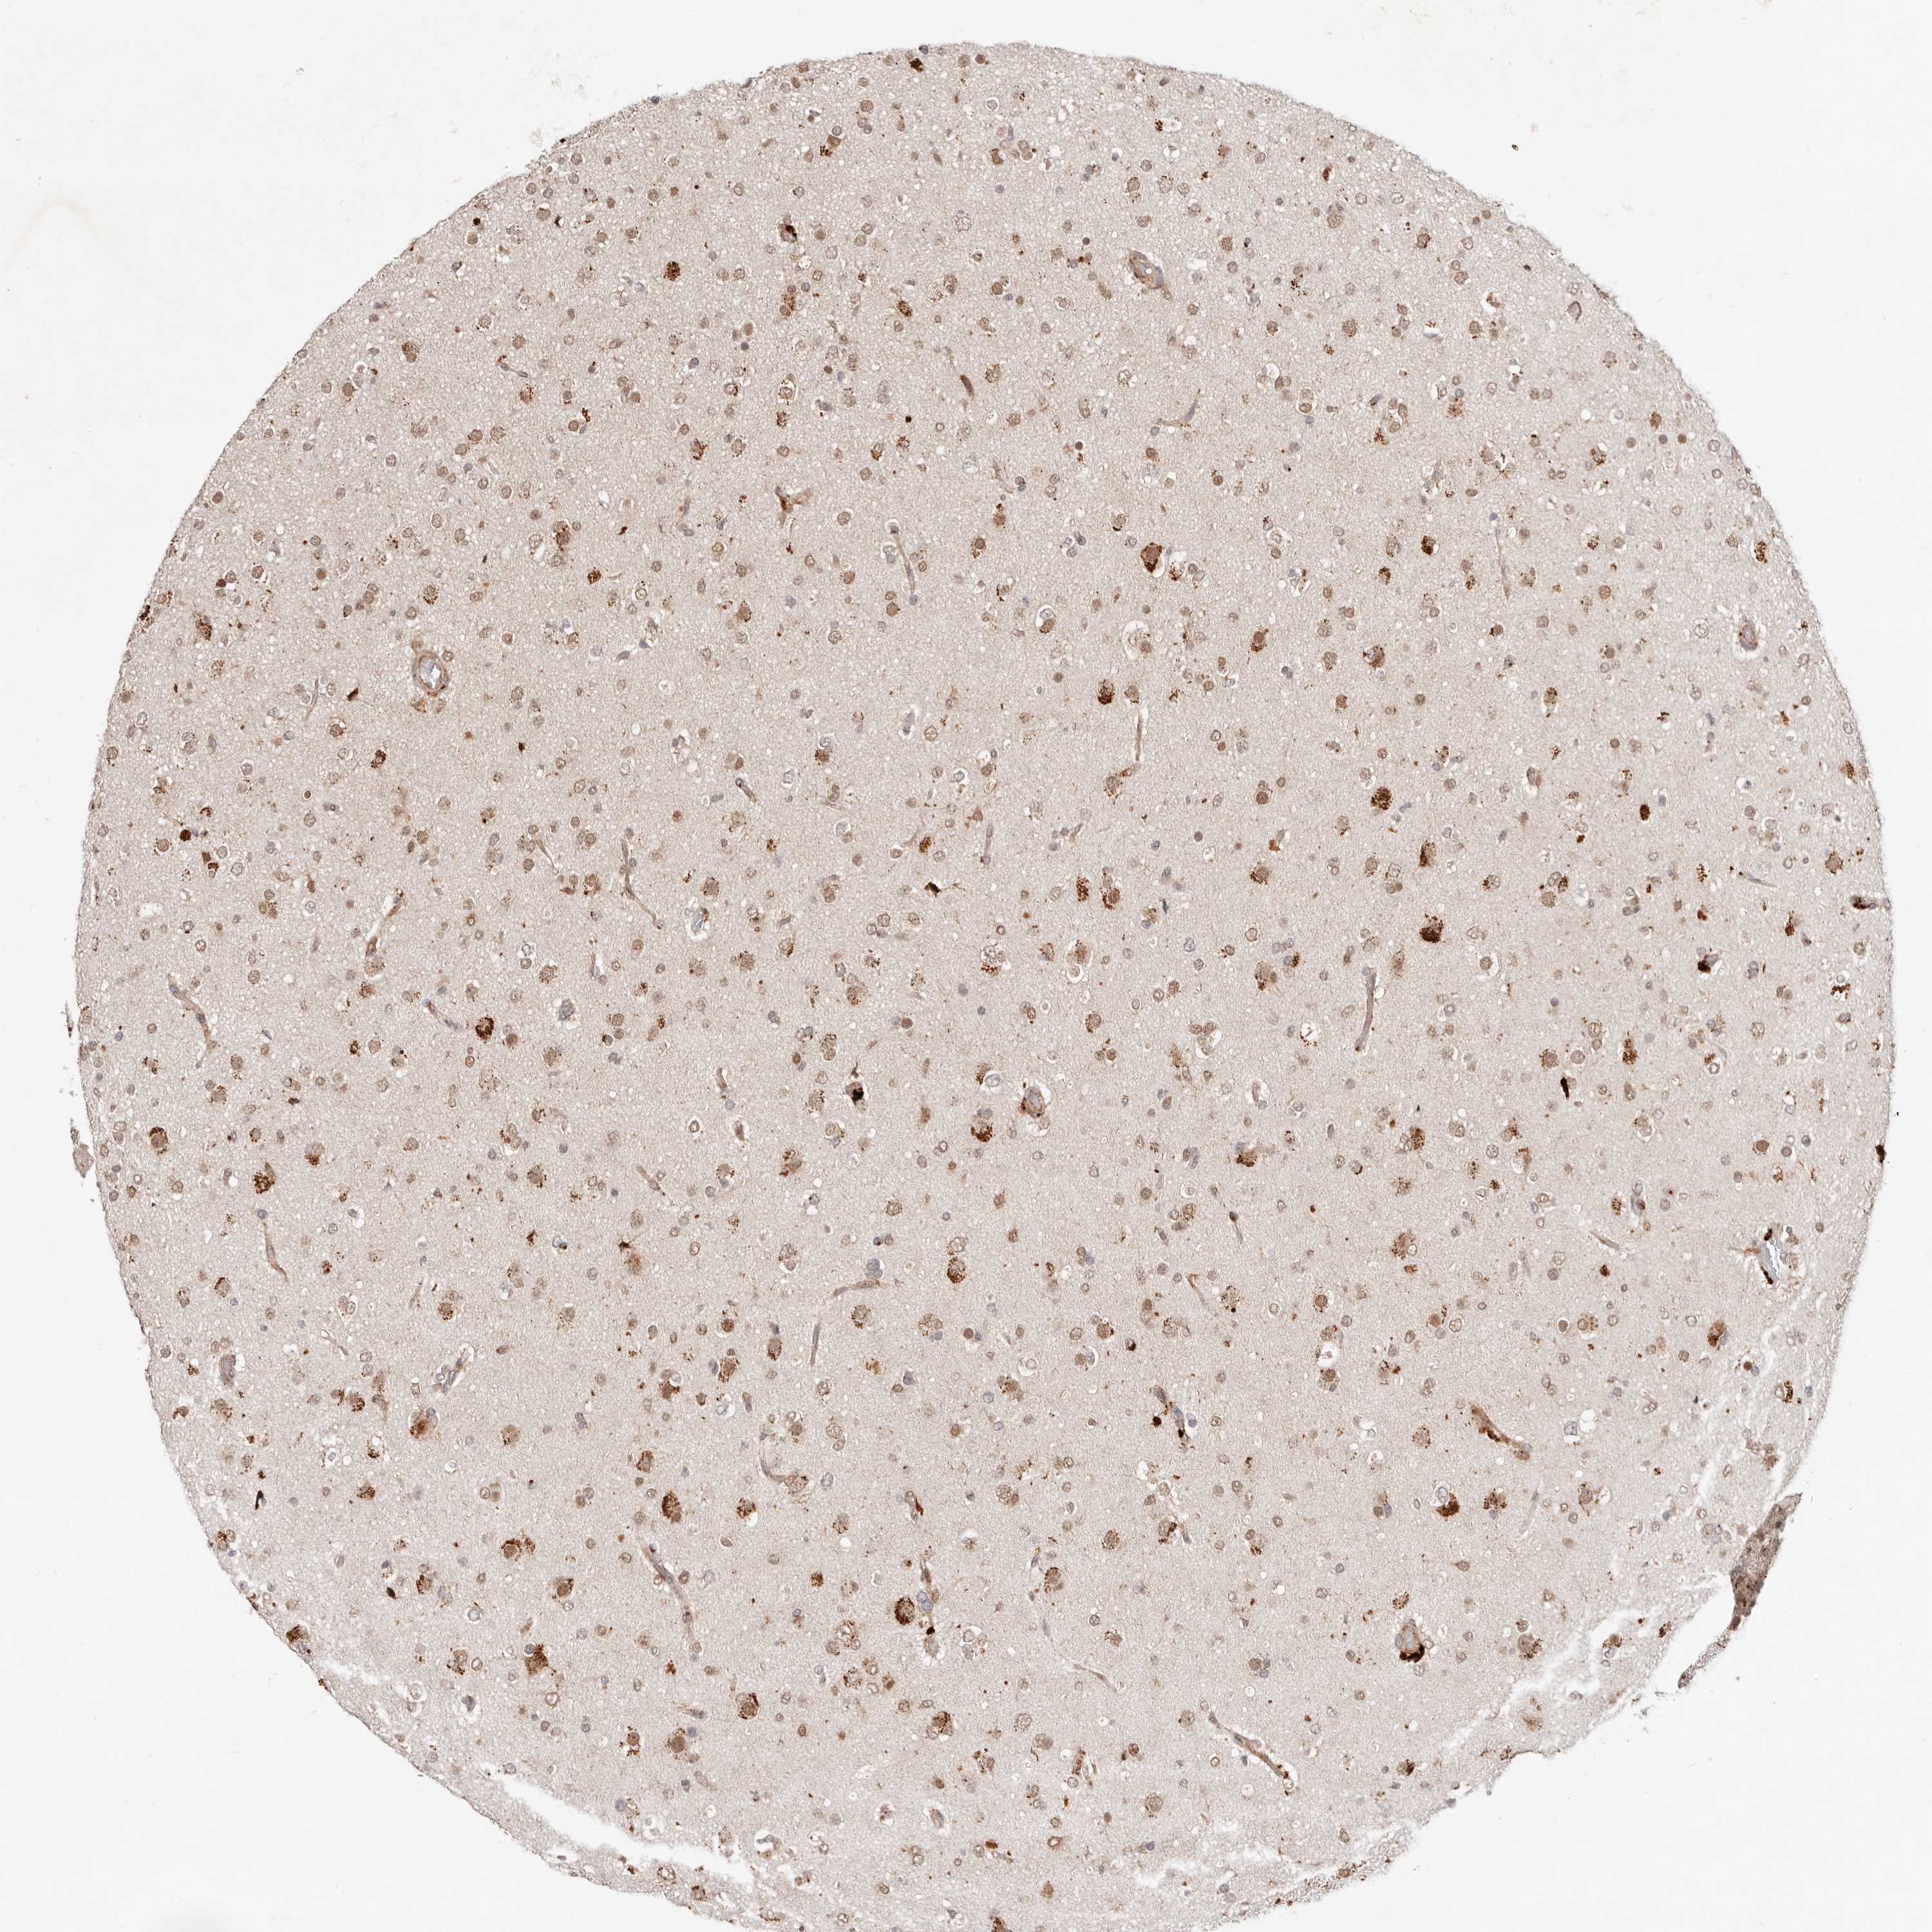

GLIOMA - Protein expressioni

A mouse-over function shows sample information and annotation data. Click on an image to view it in a full screen mode. Samples can be filtered based on level of antibody staining by selecting one or several of the following categories: high, medium, low and not detected. The assay and annotation is described here.

Note that samples used for immunohistochemistry by the Human Protein Atlas do not correspond to samples in the TCGA dataset.

Antibody stainingi

Antibody staining in the annotated cell types in the current human tissue is reported as not detected, low, medium, or high, based on conventional immunohistochemistry profiling in selected tissues. This score is based on the combination of the staining intensity and fraction of stained cells.

Each image is clickable and will lead to virtual microscopy that enables deeper exploration of all samples and also displays staining intensity scores, fraction scores and subcellular localization as well as patient and tissue information for each sample.

Antibody HPA029732

Antibody HPA029733

Staining

High

Medium

Low

Not detected

Intensity

Strong

Moderate

Weak

Negative

Quantity

>75%

75%-25%

<25%

None

Location

Nuclear

Cytoplasmic/membranous

Cytoplasmic/membranous,nuclear

Glioma, malignant, High grade

Glioma, malignant, Low grade

Glioblastoma, NOS